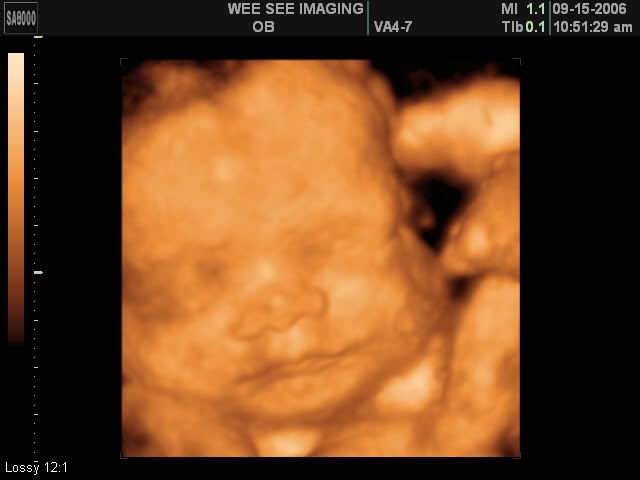

Victoria Rose Kelly

Date Due: December 15, 2006